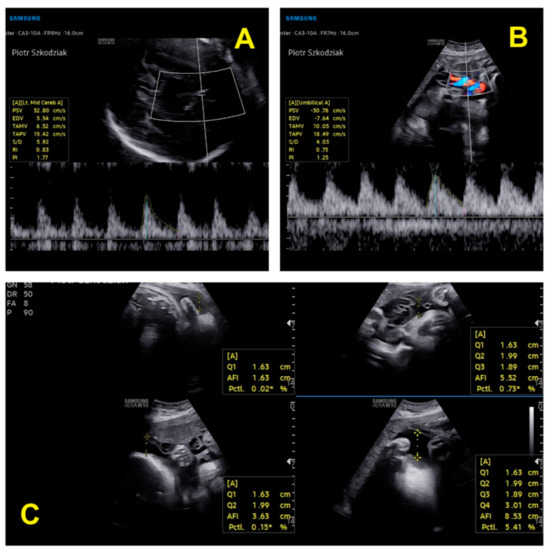

| Parameter | Twin 1 in Trimester II | Twin 2 in Trimester II | Twin 1 in Trimester III | Twin 2 in Trimester III |

|---|---|---|---|---|

| BPD (mm) (biparietal diameter) | 58.7–23w1d | 57–22w5d | 76.4–29w3d | 75.3–29w0d |

| HC (mm) (head circumference) | 221–24w1d | 207–22w6d | 275.3–29w3d | 261–27w6d |

| FL (femur length) (mm) | 40.8 mm–23w1d | 37.6–22w0 | 54.9–29w2d | 51.6–27w5 |

| AC (abdominal circumference) (mm) | 180 | 174 | 240 | 221.5 |

| AFI (amniotic fluid) | normal | normal | normal | normal |

| FHR/min (fetal heart rate) | 153 | 160 | 150 | 148 |

| EFW (g) (estimated fetal weight) | 570 | 493 | 1298 | 1057 |

| EFW discrepancy | 13.5% (assessment at 22 weeks 6 days) | 18.6% (assessment at 28 weeks 0 days) | ||